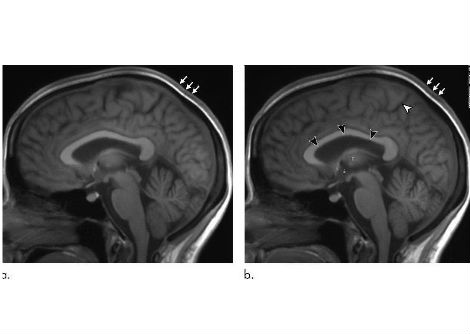

يدرس علم النفس العصبي كيف يؤثر تشريح الدماغ على سلوك الشخص وعاطفته وإدراكه. على مر السنين ، أظهر علماء الدماغ أن أجزاء مختلفة من الدماغ مسؤولة عن وظائف محددة ، سواء كان التعرف على الألوان أو حل المشكلات. على عكس أسطورة العشرة بالمائة ، أثبت العلماء أن كل جزء من الدماغ جزء لا يتجزأ من عملنا اليومي ، وذلك بفضل تقنيات تصوير الدماغ مثل التصوير المقطعي بانبعاث البوزيترون والتصوير بالرنين المغناطيسي الوظيفي.

لم تجد الأبحاث حتى الآن منطقة في الدماغ غير نشطة تمامًا. حتى الدراسات التي تقيس النشاط على مستوى الخلايا العصبية المفردة لم تكشف عن أي مناطق غير نشطة في الدماغ. تُظهر العديد من دراسات التصوير الدماغي التي تقيس نشاط الدماغ عندما يقوم الشخص بمهمة محددة كيف تعمل الأجزاء المختلفة من الدماغ معًا. على سبيل المثال ، أثناء قراءة هذا النص على هاتفك الذكي ، ستكون بعض أجزاء دماغك ، بما في ذلك تلك المسؤولة عن الرؤية وقراءة الفهم وحمل هاتفك ، أكثر نشاطًا.

ومع ذلك ، تدعم بعض صور الدماغ أسطورة 10 في المائة عن غير قصد ، لأنها غالبًا ما تظهر بقع مشرقة صغيرة على دماغ رمادي. قد يعني هذا أن النقاط المضيئة فقط لها نشاط دماغي ، لكن هذا ليس هو الحال. بدلاً من ذلك ، تمثل البقع الملونة مناطق في الدماغ تكون أكثر نشاطًا عندما يقوم شخص بمهمة ما مقارنةً مع وضع لا يقوم بذلك.